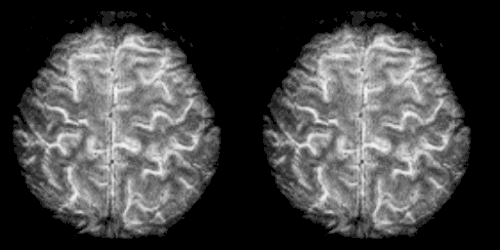

Magnetic Resonance Imaging (MRI)

Magnetic Resonance Imaging (MRI) is a medical imaging technique used to scan the brain using strong magnetic fields and radiofrequency pulses to generate signals from the brain. These signals are then detected by a radio antenna in the MRI machine and processed by computers to generate images of the brain (McIntyre & Goergen, 2017). One advantage of an MRI is that does not use x-rays or radiation such as that found in CT or PET scans which can be harmful to the body.

Functional Magnetic Resonance Imaging (fMRI)

Functional Magnetic Resonance Imaging (fMRI) involves using the same scanning machine as an MRI and overlaying a functional scan on the image. This scan is used to detect the changes in blood oxygenation in response to neural activity, indicating more active regions of the brain. fMRI is used to create activation maps that show which parts of the brain are active during different mental processes (Delvin, 2016). These activation maps make fMRIs particularly useful for researchers investigating any neurological abnormalities associated with anxiety disorders.